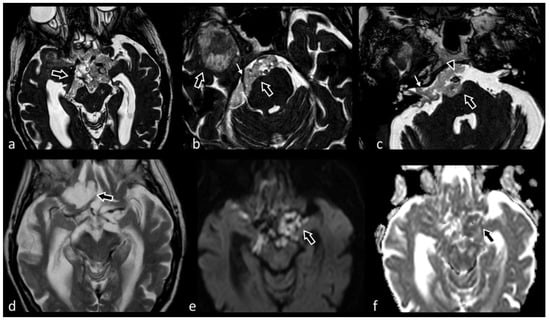

3.10. Cranio-Cervical Malformations (Chiari I)

3.12. Neonatal and Fetal MRI